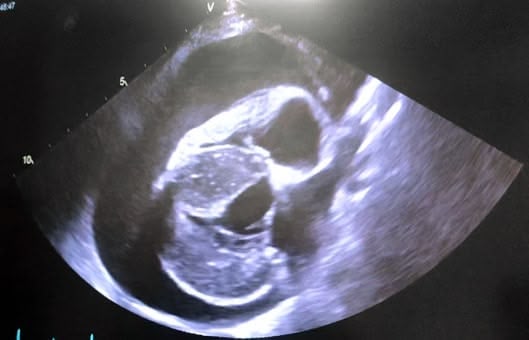

Le dernier cas de notre étude est un chat présenté pour ataxie et dont le scanner montre une fracture ponctiforme de l'os pariétal gauche du crâne avec abcès intracrânien et sous-cutané, probablement secondaires à un traumatisme. Un traitement médical est mis en place. Après une amélioration transitoire de son état général, le patient décède trois jours plus tard.